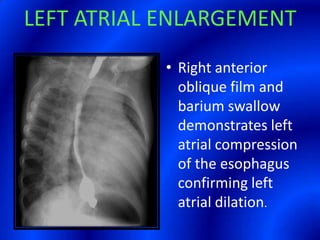

This document provides information about a barium swallow procedure. It begins with an introduction and overview of the embryology and anatomy of the pharynx and esophagus. It then describes the procedure itself, including preparation, technique, views obtained, and indications. Specific conditions that may be examined include pharyngeal and esophageal webs, foreign body impaction, scleroderma, dysphagia, mediastinal masses, and carcinoma. Diagrams are provided to illustrate normal anatomy and various pathological findings.